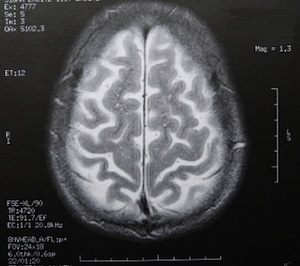

Sie sind hier: Startseite Nachrichten Gesundheit Besorgte Reaktion auf mögliche Übertragbarkeit von Alzheimer Bild: pixelio.de/Dieter Schütz